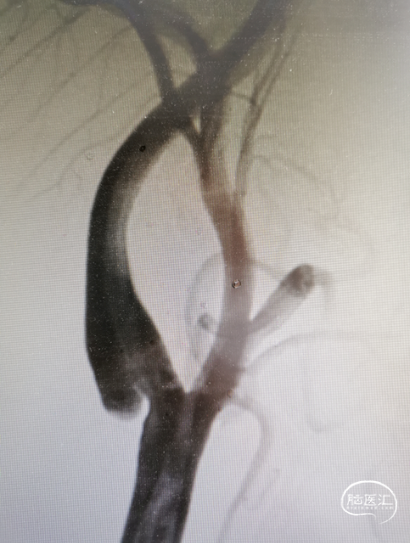

2023.12.07 行RICA支架

右侧颈内动脉起始部动脉蹼,责任血管。

右侧颈内C1段动脉支架植入术,术中造影及OCT检查若颈动脉蹼内未发现血栓,可单纯植入支架,不应用保护伞保护,也不需球囊导管预扩。

右侧颈总动脉发出右侧颈内动脉及右侧颈外动脉,右侧颈内动脉C1段、起始部侧壁可见短小薄膜样突出,颈动脉窦血流紊乱,远端血流可,大脑中动脉、大脑前动脉显影可,走形正常,未见狭窄及扩张。

使用璞慧0.014" 200cm微导丝通过右侧颈内动脉起始部,微导丝头端顺畅置于C2远端,经微导丝小心引入自膨支架(9mm×40mm)准确定位后释放于右侧颈内动脉动脉蹼处,造影显示支架贴壁良好。